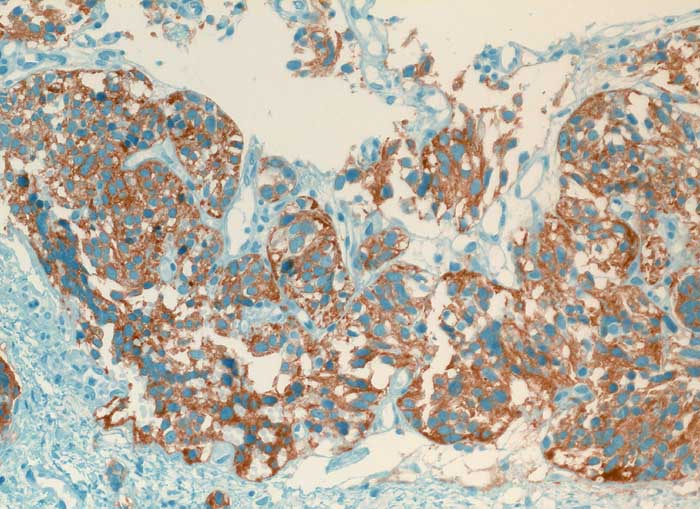

Typisches Karzinoid der Lunge

Die Diagnose hoch differenzierter neuroendokriner Tumoren ist schwierig, da ihre Oberfläche meist von Bronchialschleimhaut oder Bronchialepithel bedeckt ist und sie deswegen kaum Zellen abschilfern. Ausserdem sind die Atypien sehr diskret. Die Zellkerne sind rundlich bis oval, glatt begrenzt, fein granuliert und haben grosse Ähnlichkeit mit den Kernen von Flimmerzellen. Ohne Kenntnisse des klinischen Befundes sind Karzinoidzellen deshalb kaum von Basal- und Flimmerzellen zu unterscheiden. Der Zytoplasmasaum ist schmal und zerfällt leicht. Solche nackt liegenden Kerne können mit einem Lymphom verwechselt werden. Das typische Karzinoid hat eine sehr gute Prognose, kann aber in seltenen Fällen metastasieren. Die Unterscheidung von typischem und atypischem Karzinoid erfolgt am histologischen Schnitt durch Nachweis von Nekrosen und mehr als 3 bis 10 Mitosen pro HPF bei letzterem.